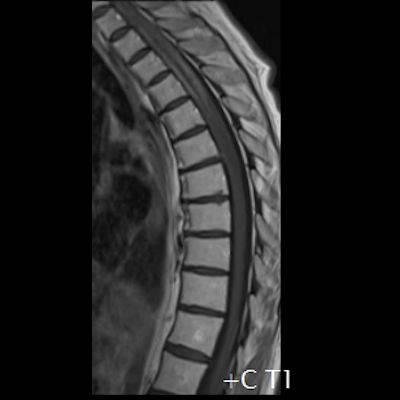

- (A) Torakal MRG’de sagital görüntülerde üst-orta torakal düzeyde T2A hiperintens (oklar), T1A izo-hipointens (ok) uzun segment ekspansil sinyal değişikliği izlenmekte olup sagital postkontrast T1A’da kontrast tutulumu mevcuttur (oklar). Bulgular longitudinal ekstensif transvers miyelit (LETM) ile uyumludur.

- Transvers miyelit sıklıkla santral gri cevheri etkileyen ve üç veya daha fazla vertebral gövde uzunluğunu etkilemektedir (LETM).

- Omurilik atrofisi ve ekspansiyon/ödem MS’e göre daha fazla görülür.

- Kontrast madde enjeksiyonu sonrasında neredeyse tüm akut NMO lezyonları, yamalı, düzensiz veya periferik olarak kontrastlanma gösterir.